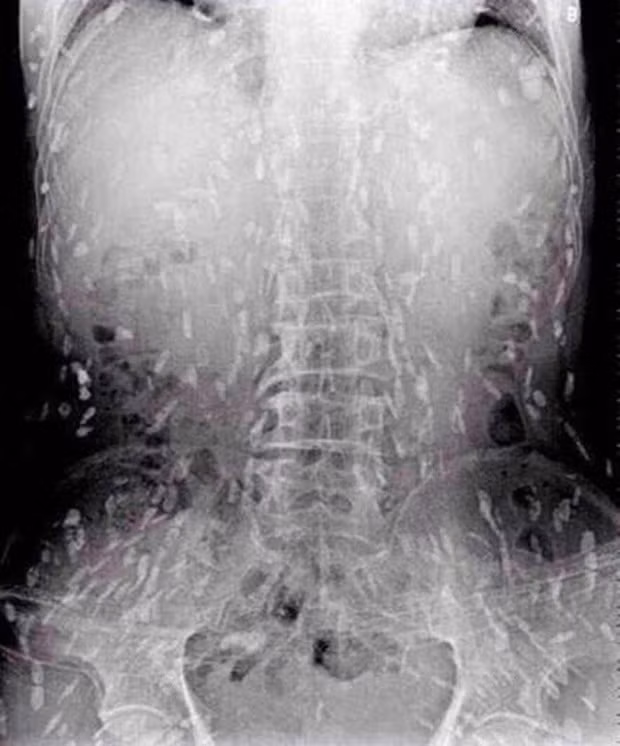

Sau khi chụp X-quang để kiểm tra, bác sĩ phát hiện gan của bệnh nhân lúc nhúc sán, được chẩn đoán mắc sán lá gan. Sán lá gan thường gặp ở các bệnh nhân ăn cá nước ngọt chưa nấu chín.

| Hình ảnh sán lúc nhúc dày đặc trong gan bệnh nhân. |

Tuy nhiên, do bệnh tình đã bước sang giai đoạn nghiêm trọng nên người đàn ông tiếp tục được chuyển tới Bệnh viện Nhân dân số 8 ở Quảng Châu để điều trị. Kết quả chụp X-quang cho thấy, những đốm trắng nhỏ xuất hiện lấm chấm khắp cơ thể chính là sán.